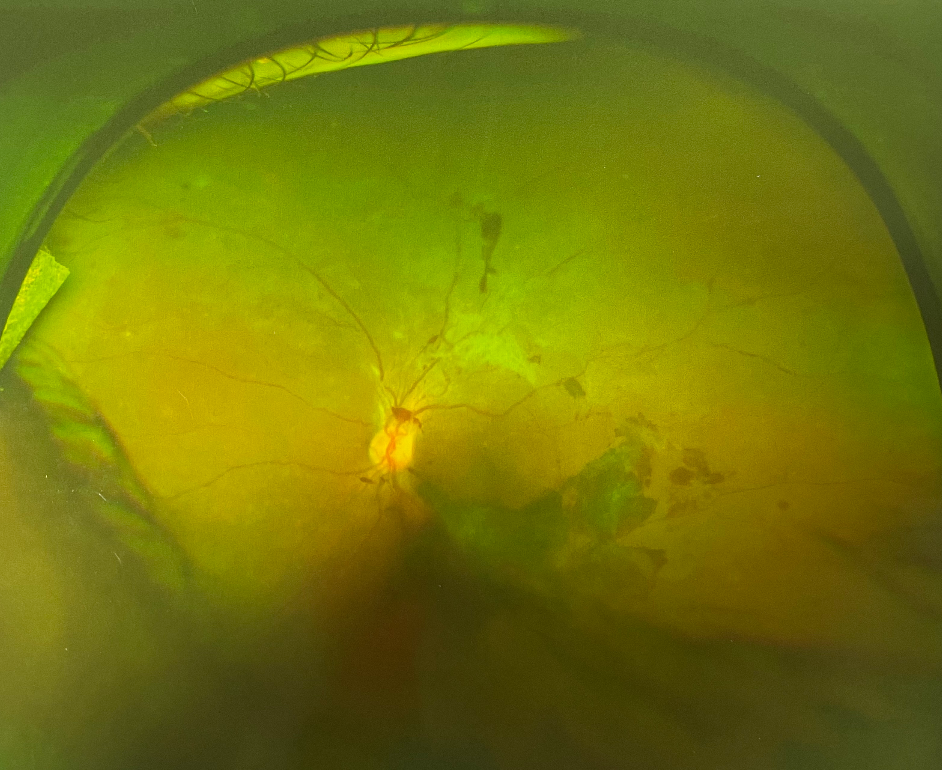

眼底出血,顧名思義就是位于眼底出的血,從外表上看不見(jiàn)。那些從外觀上看得到的出血反而不是眼底出血,而是結(jié)膜下出血(也就是眼白的地方出血)。結(jié)膜下出血一般不會(huì)影響視力,而且只要不是反復(fù)出血,一般十天左右可以消退至不留痕跡,但眼底出血是會(huì)明顯影響視力。

在患眼底病的人群中,眼底出血是非常常見(jiàn)的。但是眼底出血不是獨(dú)立的眼病,而是許多眼病和某些全身性疾病所共同的表現(xiàn)。根據(jù)出血部位的不同,一般可分為視網(wǎng)膜內(nèi)出血、視網(wǎng)膜前出血和玻璃體內(nèi)出血三種。在臨床上,比較常見(jiàn)的引起眼底出血的有視網(wǎng)膜靜脈周?chē)?、視網(wǎng)膜靜脈阻塞、視盤(pán)血管炎(靜脈阻塞型)、老年性黃斑病變、眼外傷和一些全身系統(tǒng)疾病(包括糖尿病、高血壓、腎病、白血病等)引起的眼底病變等,另外,高度近視由于眼軸變長(zhǎng)、血管被牽拉,在劇烈運(yùn)動(dòng)時(shí)也容易出現(xiàn)眼底出血。

應(yīng)該注意的是,少量的眼底出血通常沒(méi)有明顯的感覺(jué),如早期糖網(wǎng)引起的出血就常被忽視,出血量較多時(shí),會(huì)感到有紅色的影子在跳動(dòng),視線被黑影擋住。如果出血位于黃斑區(qū)(黃斑區(qū)為視力敏感區(qū),因此任何累及黃斑部病變都會(huì)引起中心視力明顯下降、視物變暗、變形等)則中心視力喪失,只有周邊有部分視力。

出現(xiàn)眼底出血,一定要到醫(yī)院仔細(xì)檢查,確診是什么病,以便對(duì)癥治療。貢主任表示,眼底出血量少的會(huì)自行吸收,出血點(diǎn)在黃斑旁邊,視力無(wú)影響的眼底出血,可以進(jìn)行激光治療治療,如若發(fā)展到黃斑變性,甚至惡化嚴(yán)重影響視力的,則需根據(jù)實(shí)際情況進(jìn)行手術(shù)。

溫馨提醒:眼底出血是沒(méi)有辦法用肉眼觀察的,通常是在體檢或嚴(yán)重影響視力時(shí)才能發(fā)現(xiàn),卻很可能耽誤了治療。這種情況多見(jiàn)于視網(wǎng)膜分支靜脈阻塞、糖尿病和高血壓病眼底出血未波及黃斑區(qū)的患者,所以糖尿病和高血壓病患者定期檢查眼底顯得很重要。